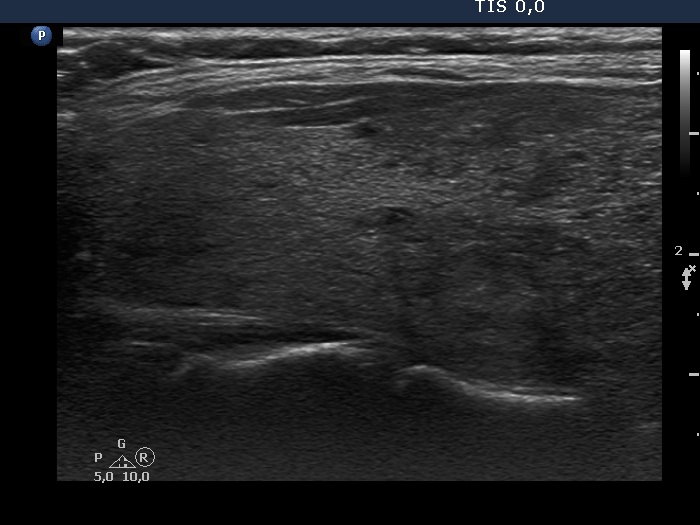

Consecutive patients with Hashimoto's thyroiditis - Case 21. (ultrasonographic picture 8)

Upper part of the left lobe, longitudinal scan.